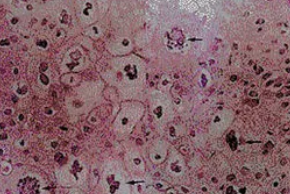

尖锐湿疣小疹是尖锐湿疣是很普遍的病症,像淡红色小丘疹,之后慢慢扩大增加,表层凸凹不平,结合成乳 头状、菜花状赘生物或鸡冠状增生,根处有蒂,其分必物侵润呈乳白色,污深灰色或鲜红色,会有痒感、灼痛和恶臭味。

尖锐湿疣典型性临床症状是初起为细微散在的乳 头状疣,绵软,其上面有细微的指样凸起,或者是为小而尖的丘疹,质稍硬,独立、散在或呈簇状,粉红色或乳白色。疾病慢慢扩大、增加,相互之间结合成鸡冠状或菜花状赘生物,顶部可有角质化或感染破溃。宫颈变病多见平扁状,人眼无法发觉,常需yin道镜检查及冰醋酸实验帮助发觉。

女士尖锐湿疣危险期均值为2-3月,变病发展趋势无自限性,病症为部分发痒、疼痛,极少数患者没有症状的。生长发育位置:私处、yin道内、宫颈、肛门周围,普遍2个位置另外产生,部分主要表现为暗红色或深灰色小疹,呈疣状凸起,常结合产生菜花式赘物。